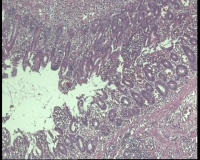

镜下穿孔周围小肠粘膜正常,见两个炎性小息肉,肠腔无狭窄,无溃疡,周围肠壁中性粒细胞,嗜酸性粒细胞浸润,淋巴细胞少,无非干酪样坏死性肉芽肿,浆膜见脓汁聚集,大量中性粒细胞浸润,并见植物细胞(黄色核的是什么细胞?图14-18),穿孔处最深处浆膜见小肠腺体(图9),穿孔原因是什么那?克隆氏病,肠结核,肠伤寒都不符,溃疡性结肠炎也不符,穿孔周围粘膜正常,无溃疡,只是穿孔的瘘道内壁炎性坏死,这个怎么报哪?阑尾仅浆膜血管充血,出血,阑尾无炎症,那右下腹痛就不是阑尾炎,是回肠末端穿孔,回肠末端要是炎症穿孔的话,周围粘膜得有坏死,这个都正常啊,况且穿孔深处底端的小肠粘膜都是正常的腺体,就好像粘膜缺失的组织沿着空腔掉到了浆膜,小肠漏出少量内容物,浆膜周围化脓性炎,坏死,形成包裹,这怎么报告那?

• 图9穿孔深处浆膜内腺体